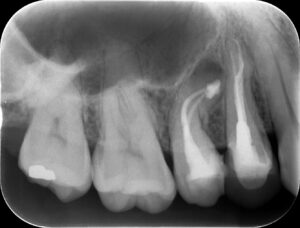

極度に湾曲した歯の治療〜ダブルカーブを攻略できるのか? #4 RCT⇨Apicoectomy

バイト先での治療。 主訴は、 右上で咬合すると痛い である。 歯内療法学的検査(2023.2.9) #3 Cold+3/3, Perc.(-), Palp.(-), BT(-), Perio probe(WNL), Mo … 続きを読む 極度に湾曲した歯の治療〜ダブルカーブを攻略できるのか? #4 RCT⇨Apicoectomy